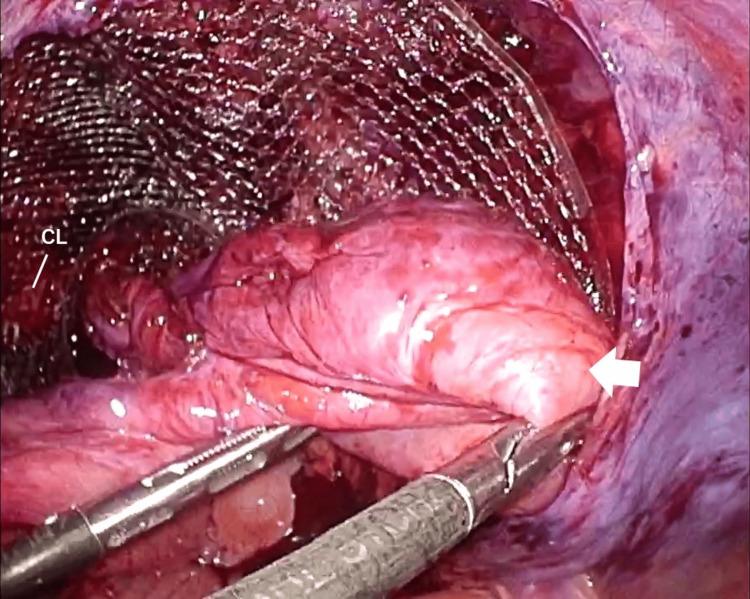

Here, we report a case of laparoscopic trans-inguinal hernia repair (transabdominal preperitoneal repair or TAPP) for a recurrent inguinal hernia following direct Kugel surgery. A 71-year-old man underwent direct Kugel hernioplasty for a right inguinal hernia at another hospital 4 years prior to presentation. The patient subsequently underwent laparoscopic surgery using the TAPP technique, during which the abdominal cavity was visualized with a laparoscope, revealing a tubular mesh protruding towards the abdominal cavity with a direct and indirect hernia ring. Three months post-surgery, no recurrence was observed.

在此,我们报告一例针对直接Kugel手术后复发性腹股沟疝的腹腔镜经腹股沟疝修补术(经腹腹膜前修补术或TAPP)。一名71岁男性在就诊前4年于另一家医院接受了右侧腹股沟疝的直接Kugel疝修补术。该患者随后接受了使用TAPP技术的腹腔镜手术,术中通过腹腔镜观察腹腔,发现一个管状补片向腹腔突出,伴有直疝和斜疝疝环。术后三个月,未观察到复发。